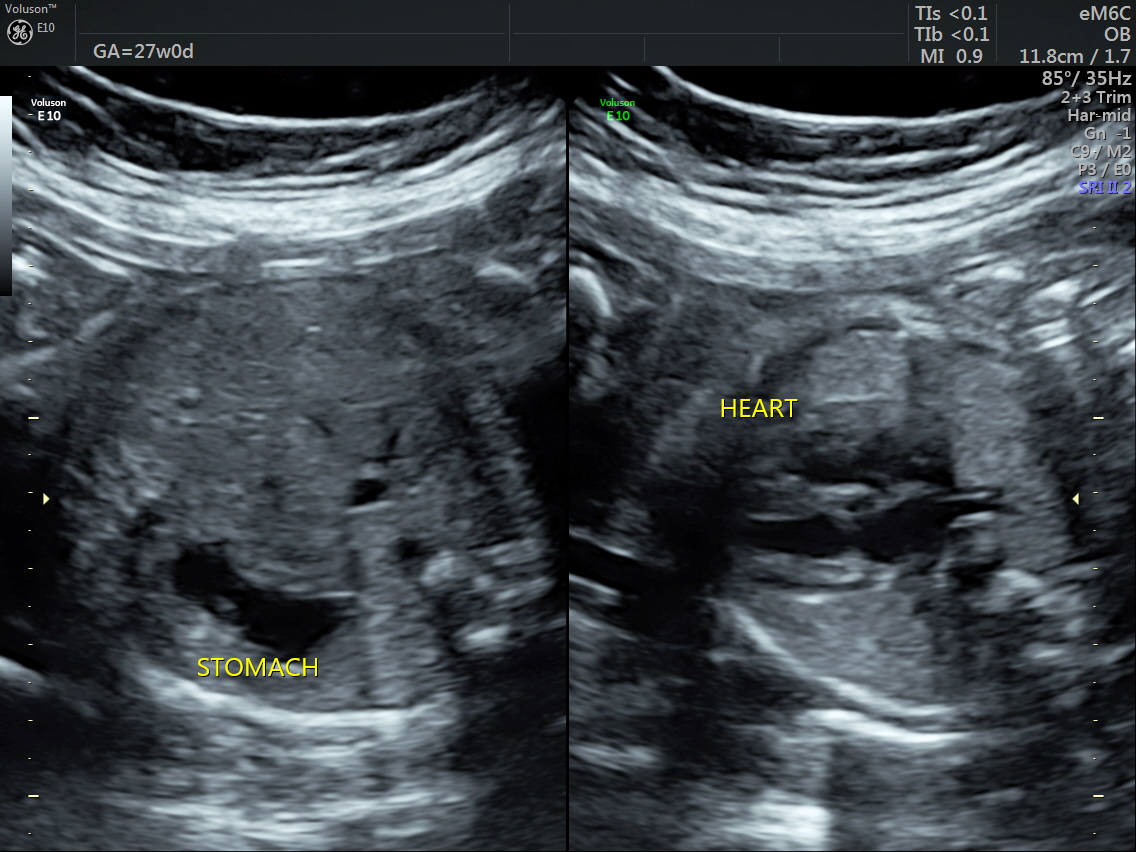

RT AORTIC ARCH_8 Published June 17, 2016 at 1136 × 852 in Rt aortic arch and aberrant left subclavian artery ← Previous Next →